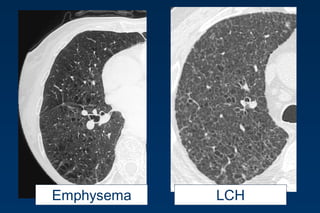

LCHEmphysema

Emphysema typically presents as

areas of low attenuation without

visible walls as a result of

parenchymal destruction.